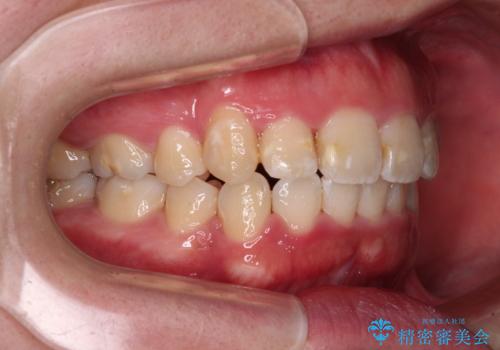

- 上下の八重歯やデコボコを気にして来院された患者様です。

上下ともに八重歯が顕著であったので、上下左右第一小臼歯4本を抜歯し、補助装置を使用して速やかに改善しながら、ワイヤー装置にて矯正治療を行うこととしました。

気になっていた八重歯は装置装着から3か月ほどで解消されました。

2年以内を目標として治療を開始しましたが、1年半ほどで終えることができました。